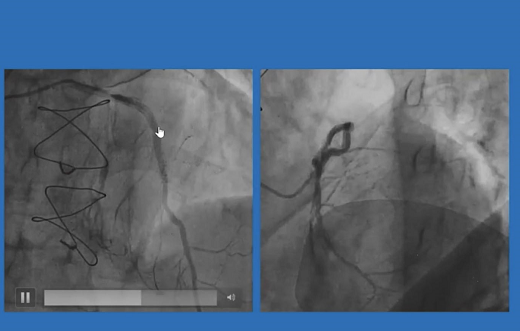

患者及家属拒绝外科搭桥手术,遂决定在ECMO支持下进行旋磨。多次旋磨后成功恢复血流,且未见夹层和血肿形成。术后1年复查造影未见明显狭窄,患者生活质量大大改善。

遂决定术前在股动脉处预埋两把血管缝合器,在ECMO支持下先对LAD病变进行了血运重建,患者术中血流动力学稳定,术后导管室即刻拔管并缝合血管。一个月后行择期PCI开通RCA闭塞病变。

本次入院后对外周动脉进行评估,遂在行PCI时植入ECMO提供血流动力学支持,成功对LAD钙化病变进行了旋磨治疗。术中全程患者生命体征稳定,术后即刻拔除ECMO。